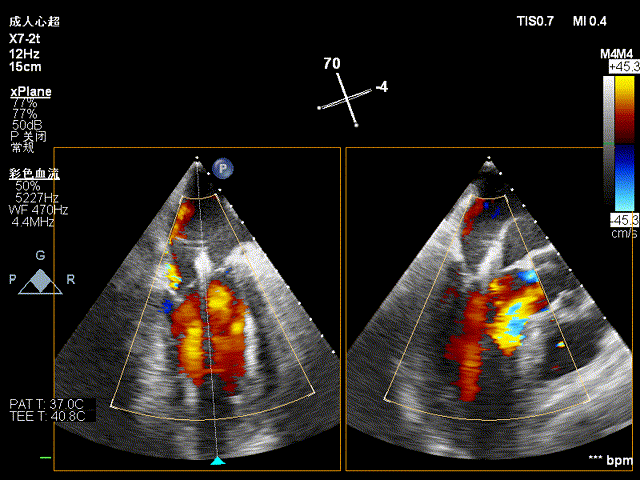

超声显示:升主动脉34mm、窦部34mm,左房(前后/横径) 41/40mm,左室(舒张期/收缩期)58/37 mm,EF 66%。彩色多普勒显示主动脉瓣和二尖瓣反流。

超声提示:左心增大;心脏瓣膜病,主动脉瓣中重度关闭不全,二尖瓣中度关闭不全。

术前超声见主动脉瓣反流:

二尖瓣中大量反流: